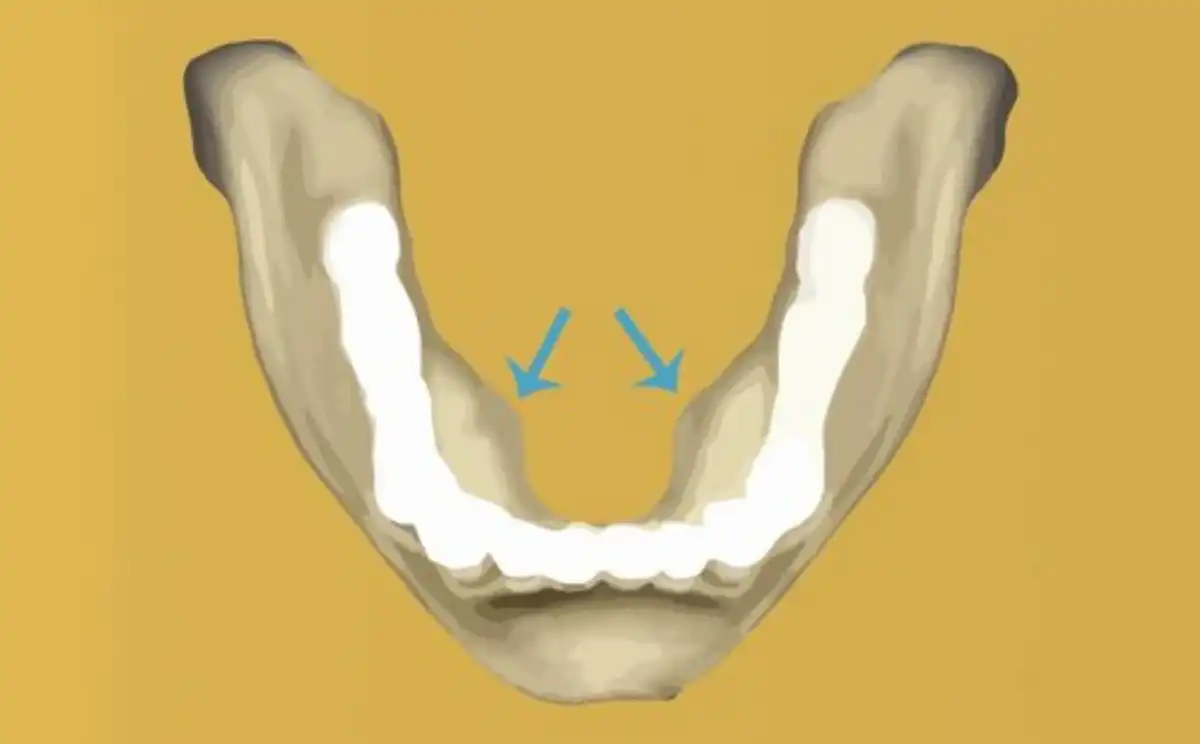

What are Mandibular Tori?

Mandibular tori (tori bone) is a bony overgrowth just inside the floor of the mouth on the tongue-side surface of the mandibular bone (lower jaw.)Subscribe for dental tips